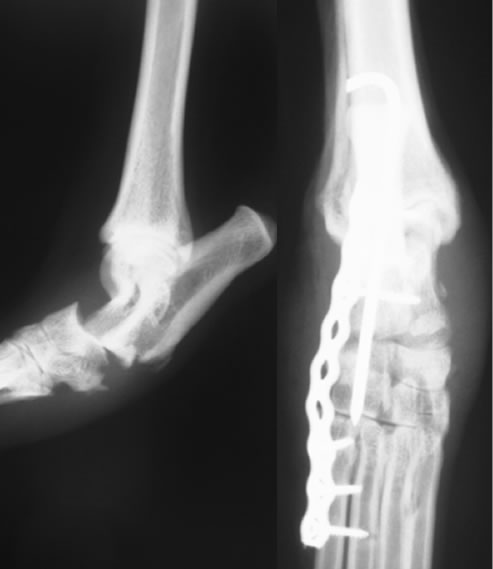

足根関節脱臼 / 不安定症

足根関節脱臼 / 不安定症とは

落下やジャンプに伴って起こる靭帯の損傷や免疫介在性関節炎、糖尿病・クッシング症候群など内科疾患に関連して起こる靭帯の変性などによって生じる足根関節の不安定性。

治療

外科適応の場合は全関節固定術、部分関節固定術、スーチャーアンカー法などをおこない、足根関節を固定します。